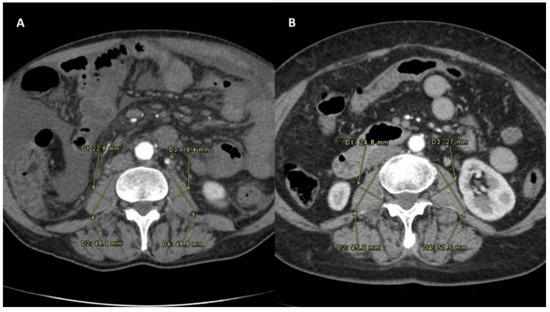

2.2. Sarcopenia Measurement